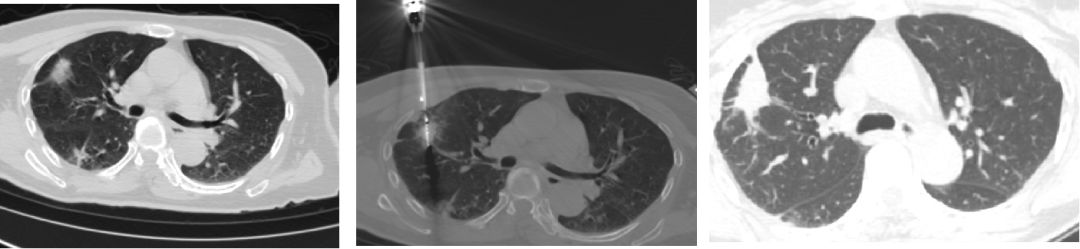

此外,基于钝性圆头微波针安全性良好的特征,池嘉昌副教授提出了消融后同步活检的新诊疗模式,即先凝固、后取样、再消融治疗,同时间做到了GGO的取样和治疗。

与常规活检进行对比,凝固后活检不仅穿刺活检造成的出血大大减少,同时由于病灶皱缩变成实性病灶,活检的取样量明显增加,而低功率的微波凝固方法不会影响病理诊断和相关基因检测的结果,大大提高了穿刺成功率和安全性。

常规活检 vs 消融后活检(更多更致密的标本)